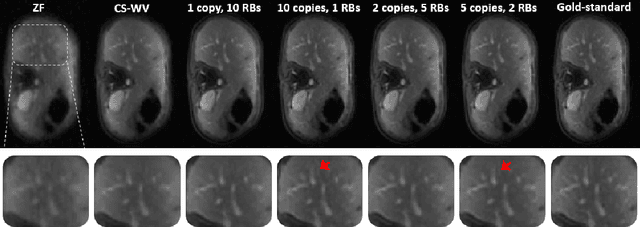

Abstract:Recovering high-resolution images from limited sensory data typically leads to a serious ill-posed inverse problem, demanding inversion algorithms that effectively capture the prior information. Learning a good inverse mapping from training data faces severe challenges, including: (i) scarcity of training data; (ii) need for plausible reconstructions that are physically feasible; (iii) need for fast reconstruction, especially in real-time applications. We develop a successful system solving all these challenges, using as basic architecture the recurrent application of proximal gradient algorithm. We learn a proximal map that works well with real images based on residual networks. Contraction of the resulting map is analyzed, and incoherence conditions are investigated that drive the convergence of the iterates. Extensive experiments are carried out under different settings: (a) reconstructing abdominal MRI of pediatric patients from highly undersampled Fourier-space data and (b) superresolving natural face images. Our key findings include: 1. a recurrent ResNet with a single residual block unrolled from an iterative algorithm yields an effective proximal which accurately reveals MR image details. 2. Our architecture significantly outperforms conventional non-recurrent deep ResNets by 2dB SNR; it is also trained much more rapidly. 3. It outperforms state-of-the-art compressed-sensing Wavelet-based methods by 4dB SNR, with 100x speedups in reconstruction time.

Abstract:Recovering images from undersampled linear measurements typically leads to an ill-posed linear inverse problem, that asks for proper statistical priors. Building effective priors is however challenged by the low train and test overhead dictated by real-time tasks; and the need for retrieving visually "plausible" and physically "feasible" images with minimal hallucination. To cope with these challenges, we design a cascaded network architecture that unrolls the proximal gradient iterations by permeating benefits from generative residual networks (ResNet) to modeling the proximal operator. A mixture of pixel-wise and perceptual costs is then deployed to train proximals. The overall architecture resembles back-and-forth projection onto the intersection of feasible and plausible images. Extensive computational experiments are examined for a global task of reconstructing MR images of pediatric patients, and a more local task of superresolving CelebA faces, that are insightful to design efficient architectures. Our observations indicate that for MRI reconstruction, a recurrent ResNet with a single residual block effectively learns the proximal. This simple architecture appears to significantly outperform the alternative deep ResNet architecture by 2dB SNR, and the conventional compressed-sensing MRI by 4dB SNR with 100x faster inference. For image superresolution, our preliminary results indicate that modeling the denoising proximal demands deep ResNets.